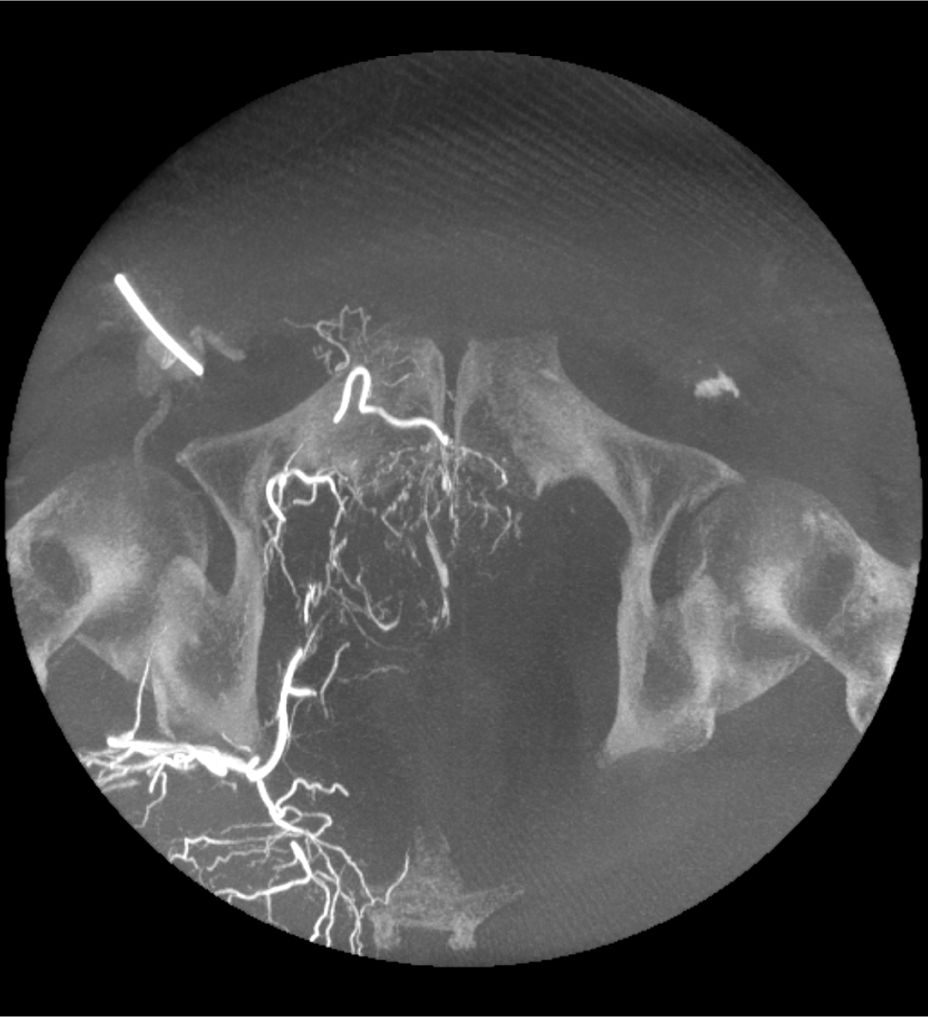

3D CT HD5

Optimierung von Diagnosen, chirurgischen Planungen, interventionellen Verfahren und Nachfolgeuntersuchungen

3D CT HD5 ist eine Option, die auf fortschrittlichen Algorithmen basiert. Diese Algorithmen verbessern die Visualisierung von Weichgewebe, reduzieren Rauschen und minimieren Artefakte, die den Visualisierungskomfort beeinträchtigen können. 3D CT HD bietet eine qualitativ hochwertige Bildgebung von internen Körperstrukturen einschließlich Gefäßen, Knochen und Weichgewebe. Mit dieser Funktion können Ärzte auf Aufnahmen von hoher Qualität zugreifen und fundierte Entscheidungen treffen.

3D CT HD5: Enhanced soft-tissue visualization and noise reduction for high-quality CBCT imaging